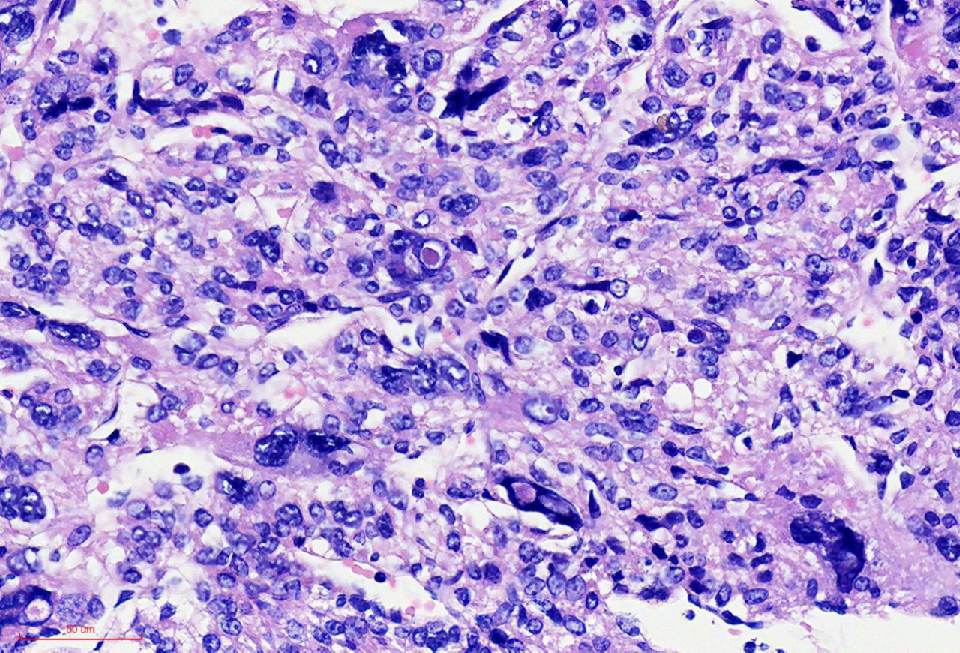

组织学改变

肿瘤与周围境界清楚

肿瘤细胞丰富

瘤细胞排列呈血管外皮瘤样

瘤细胞疏密相间

异型明显,可见核内包涵体,红核仁

未见凝固性坏死

核分裂象数2个/10HPF